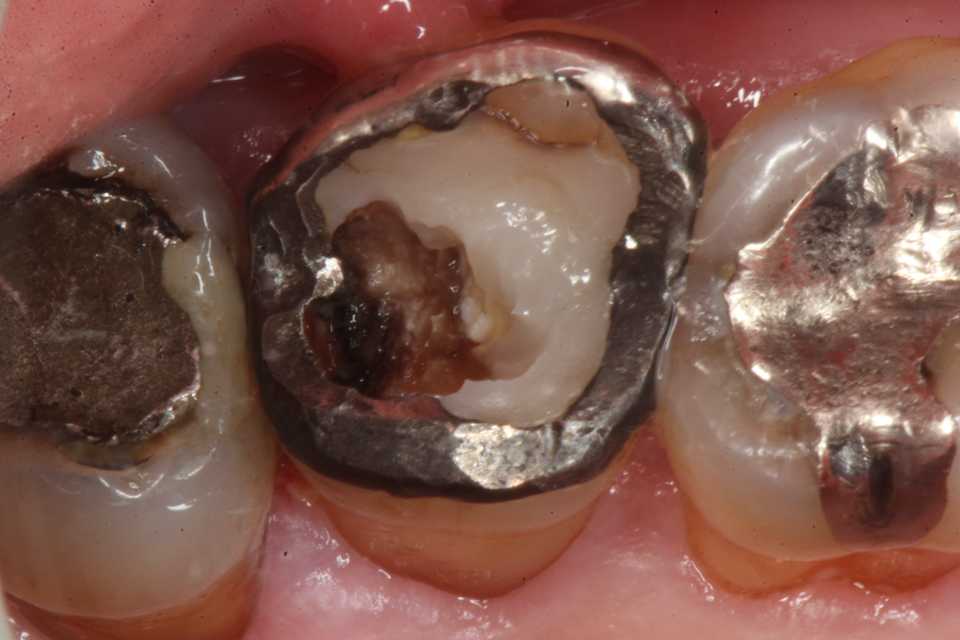

70代男性、左上7、外傷性咬合、自発痛-

応力腐食割れ ​」に似た腐食(虫歯)が発生する。

補強冠を入れて崩壊を防いでいたが、とうとう遠心隣接面が崩壊した。切削バーもスプーンエキスカベータも届きにくいし、歯肉側のエナメル質も失われていて、象牙質も軟化象牙質に近くなっている。

直視下ではこんな感じで、患部が見えないのでミラーテクニックが必要になるが、器具も届きにくいので術者も絶望的な気分になる。